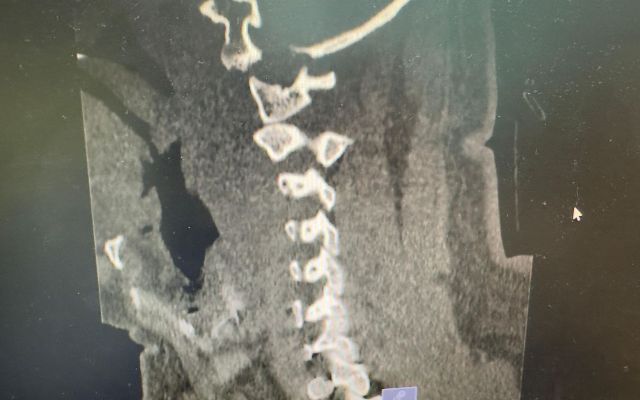

نجح – بفضل الله – الفريق الطبي في مدينة الملك سعود الطبية، عضو تجمع الرياض الصحي الأول، في إنقاذ حياة مريض تعرّض لإصابة نادرة وشديدة الخطورة تمثّلت في خلع كامل بين الرأس والرقبة (Atlanto-occipital dislocation)، وهي من أخطر الإصابات التي تهدد الحياة بشكل مباشر.

وتُصنّف هذه الحالة ضمن الحالات الطبية الحرجة عالمياً، حيث تصل نسبة الوفاة فيها قبل الوصول إلى المستشفى إلى ما بين 70% و90%، نتيجة تأثيرها المباشر على المراكز الحيوية في الجسم.

وفور وصول المريض، باشر فريق جراحة العمود الفقري التدخل بشكل عاجل، حيث أُجريت عملية جراحية معقدة ودقيقة شملت:

* إعادة المحاذاة بين الرأس والرقبة

* تثبيت الوصلة القحفية العنقية باستخدام تقنيات جراحية متقدمة